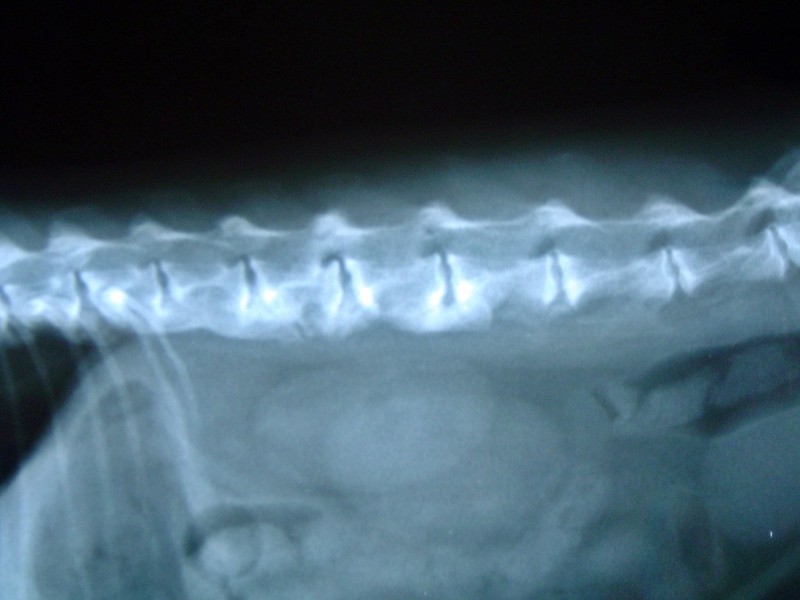

DIAGNÓSTICO POR IMAGEN.

Radiografía, ecografía, endoscopia y RMI.

(RMI, servicio concertado)